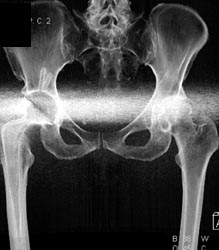

Diagnosis